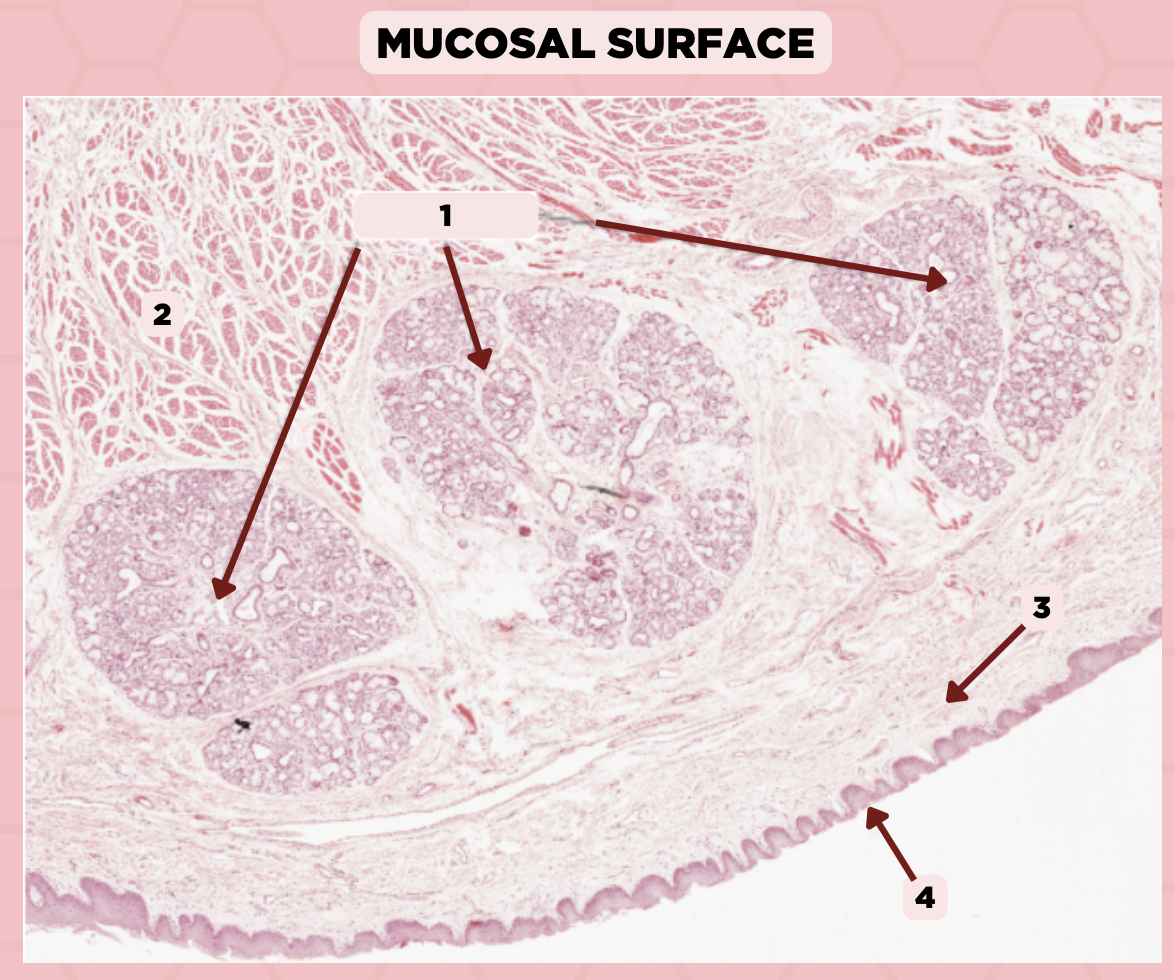

Lip

What specimen is showed in the picture?

Labial Glands (in the Mucosa)

Identify the structure labeled as 1.

Skeletal Muscle Cells

Identify the structure labeled as 2.

Lamina Propria

Identify the structure labeled as 3.

Mucosa

Identify the structure labeled as 4.

Lip

What specimen is showed in the picture?